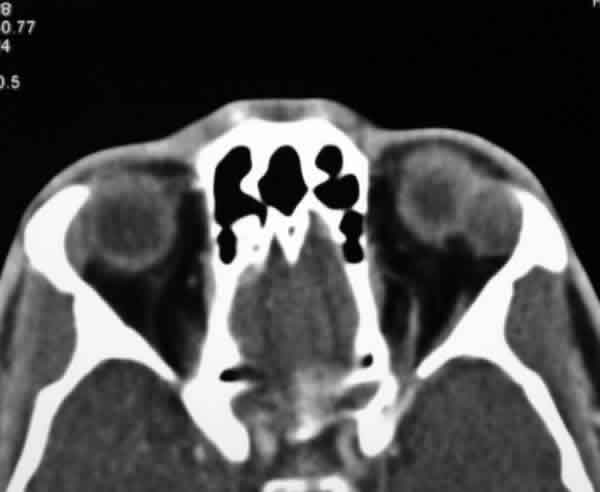

Ante la posibilidad de una estirpe maligna (dolor, radiología y aparición subaguda), se programó la cirugía en un breve período de tiempo. Se le practicó una orbitotomía lateral izquierda vía pliegue palpebral superior y risorio, con osteotomía lateral y extracción de la masa in toto (fig. 3), tras lo que se reconstruyó la pared ósea con microplacas y microtornillos. La anatomía patológica reveló un adenoma pleomórfico sin atipia ni mitosis con abundantes células mioepiteliales y de aspecto condroide (fig. 4).

Fig. 4. Patrón bifásico de células cuboideas formando ductos y estroma de hábito mixoide. H-E, 20x.